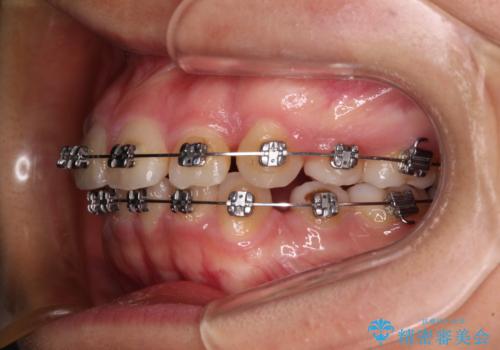

- メタルブラケット

舌の突出癖があり、咬合力も強かったため、治療期間は長くなることが懸念されましたが、舌のトレーニングをしっかりと行っていただいたこともあり、2年弱で治療を終えることができました。